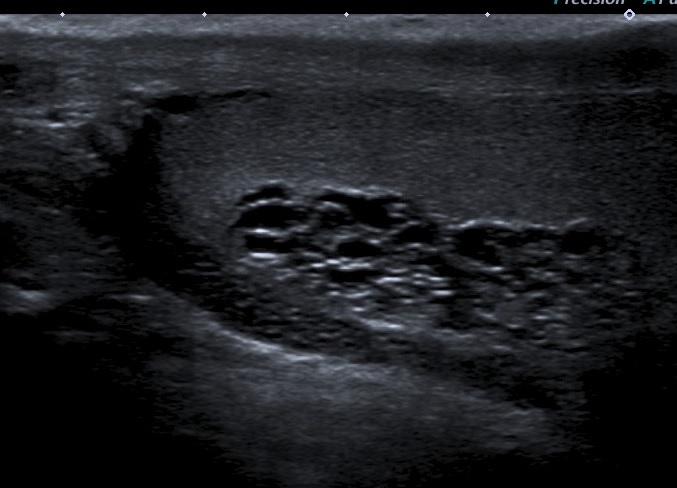

• Se realiza estudio con sonda lineal de alta frecuencia. Se explora el escroto y ambos testículos (figura 1), que presentan tamaño, morfología y ecoestructura normal, así como correcto flujo Doppler (figura 2). A nivel del teste izquierdo, se observa una colección de pequeñas imágenes anecoicas en el mediastino testicular, pseudotubulares. Además, una imagen anecoica, redondeada, quística, a nivel de la cabeza del epidídimo (figura 3).

• Se solicita ecografía testicular reglada que es informada como ectasia tubular de la rete testis en probable relación con antecedente de vasectomía y en la que se visualiza quiste de epidídimo izquierdo de 15 x 8 mm e hidrocele grado I, sin varicocele asociado.